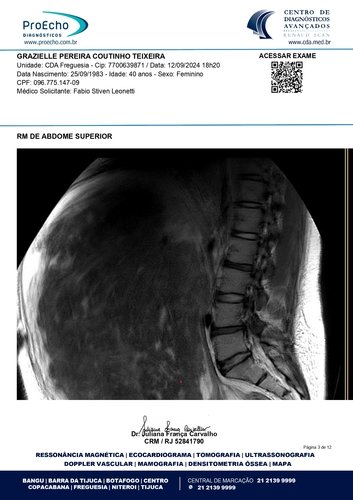

Olá, meu nome é Grazielle, tenho 41 anos e estou enfrentando a batalha mais difícil da minha vida. Fui diagnosticada com quatro miomas, sendo que o maior deles mede 30 x 20 x 28 cm e está comprimindo meus órgãos internos, além de endometriose, um cisto no ovário direito, mucocele de apêndice e um nódulo no intestino. Minha barriga está tão inchada que parece a de uma mulher grávida de 9 meses. Mas, apesar da aparência, o que mais preocupa os médicos é o apêndice inflamado. Se ele estourar, pode causar uma infecção generalizada e me levar a óbito. O tempo é curto: os médicos recomendaram que eu faça a cirurgia no máximo em três meses.

Abaixo, você encontrará os laudos médicos e imagens dos exames que comprovam o meu diagnóstico, bem como o orçamento detalhado da cirurgia. Se tiver alguma dúvida, estarei à disposição para fornecer mais informações.

Ressonância magnética: https://drive.google.com/file/d/1oSvors6sJRCRTZHVSZs9YeKzpw54SFw5/view?usp=sharing